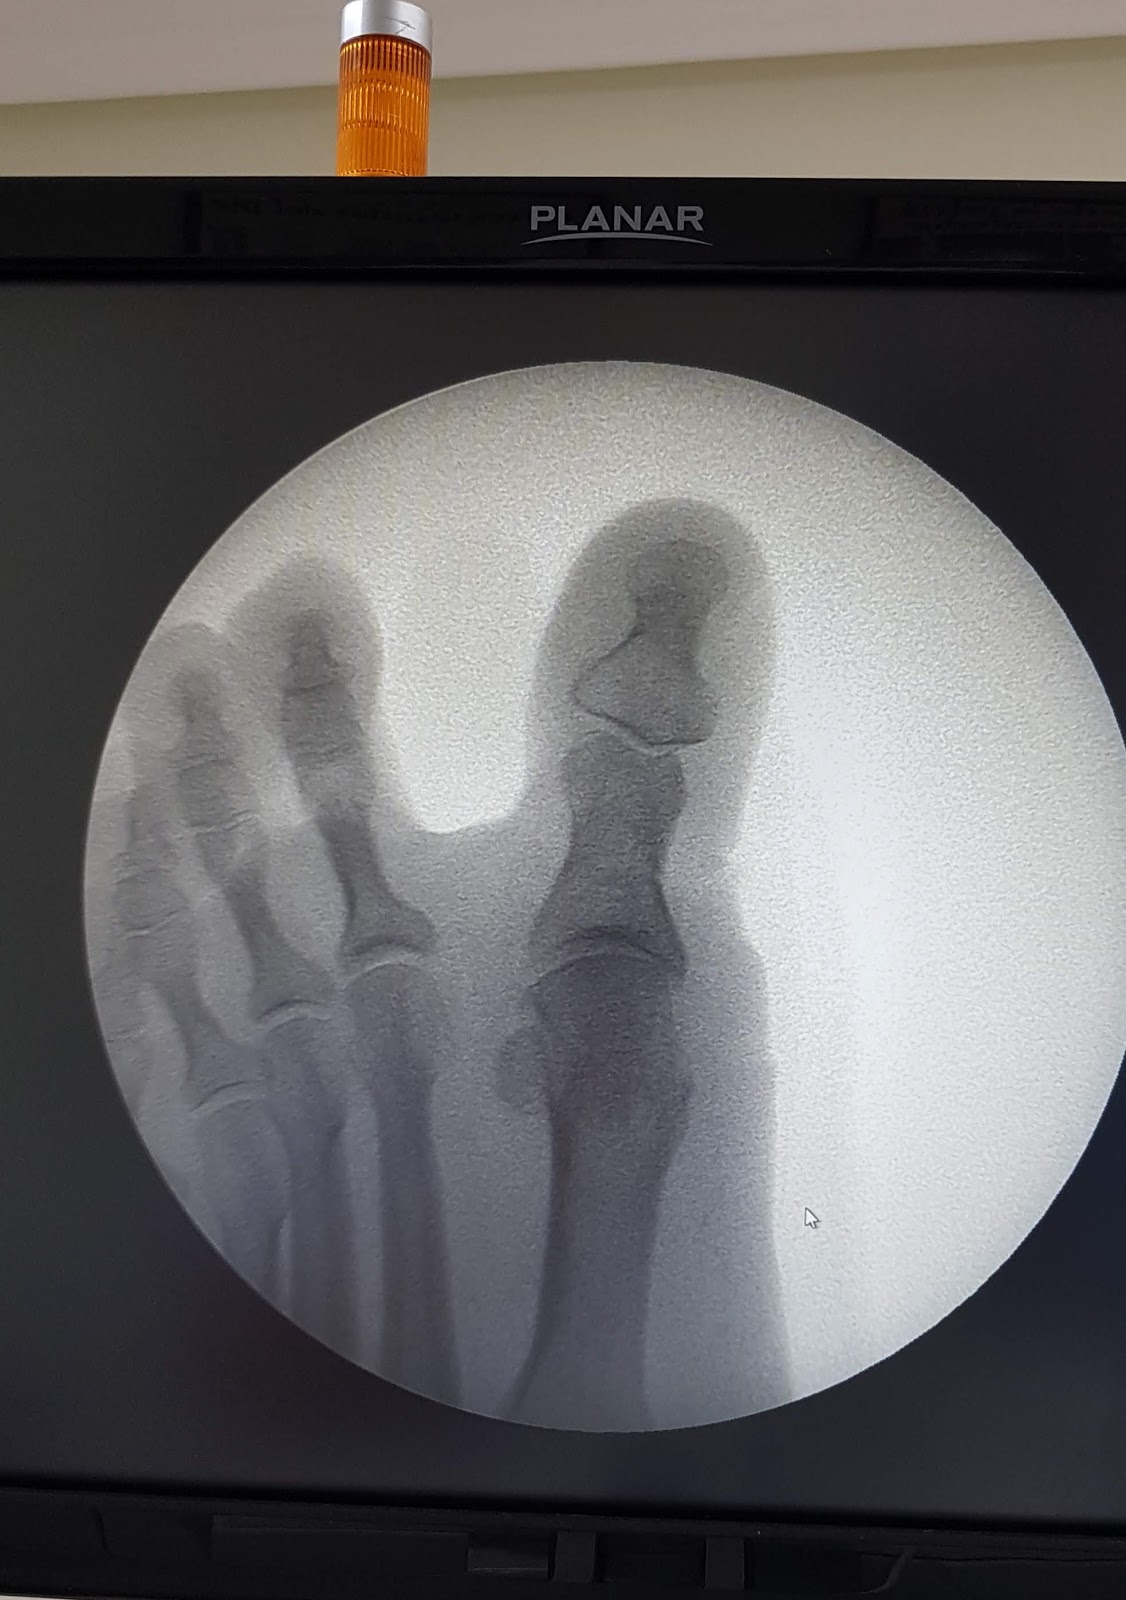

Realizo vendaje y compruebo con el fluoroscopio.

Se puede ver cono quedó alineado y sin apreciarse las osteotomías, las cuales, debido al proceso de reabsorción y remodelación, las veremos posteriormente.